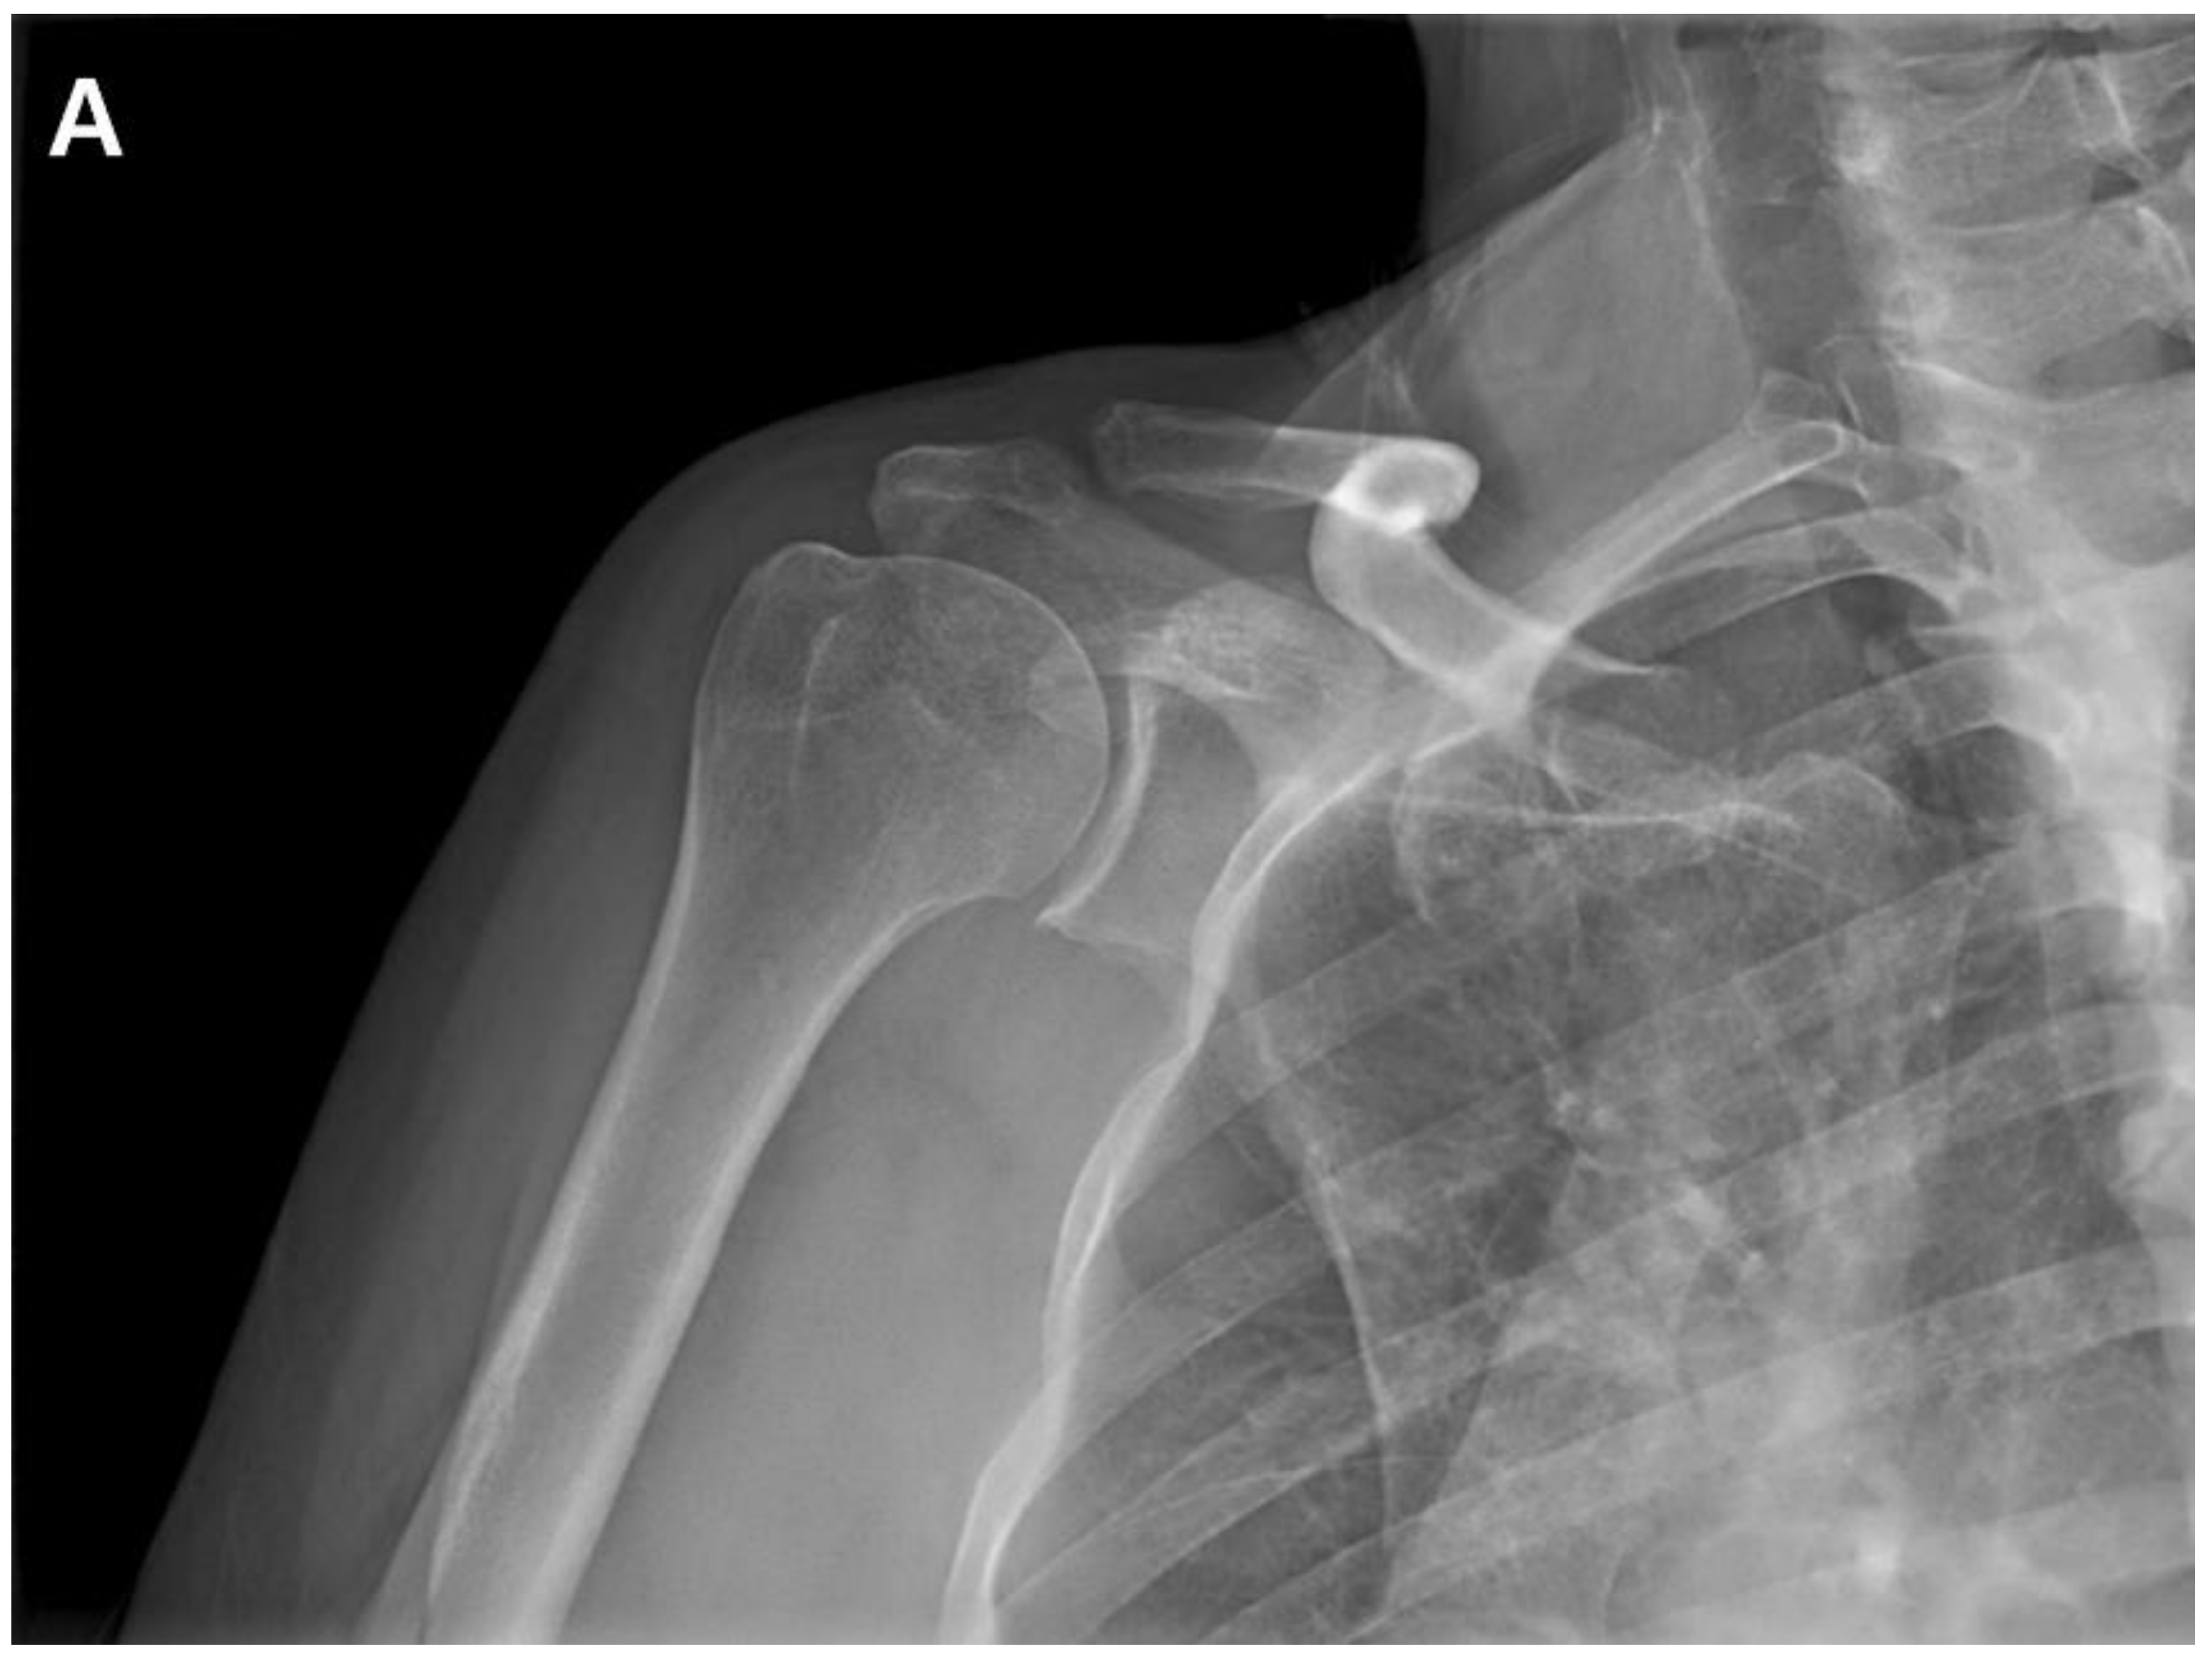

The patient returned to the hospital 21 months after the ACR with right shoulder pain. Plain shoulder anteroposterior radiography and MRI showed a subchondral cyst and a high bone marrow signal on the epiphysis of the superomedial area of the humeral head on T2-weighted images, suggesting avascular osteonecrosis of Cruess stage II (Fig. 4). The patient denied any traumatic injury, radiotherapy, exacerbation of chronic hepatitis, alcohol consumption, or use of other medications. The patient received six intra-articular injections of glucocorticoids during the 15 months of open follow-up at another institution. It is unclear whether the six intra-articular injections were corticosteroids. At 3-years postoperatively, his VAS score was 3, ASES score was 63, and CMS score was 59, indicating increased discomfort. As the patient found the discomfort tolerable in terms of both work capacity and activities of daily living, we decided to maintain the current status and continue observation until osteonecrosis progressed (Fig. 5.)

Figure 4. A. Postoperative plain radiograph obtained at 21 months post-ACR. B. Oblique coronal T1 fat-suppressed MRI. C. Oblique coronal T2 fat-suppressed MRI shows osteolytic changes in the superomedial humeral head. MRI shows cystic changes in the epiphyseal area, but articular congruity remains preserved.

Figure 5. Anteroposterior radiograph of the shoulder shows articular collapse on the superomedial side of the humeral head at 3-years postoperatively.